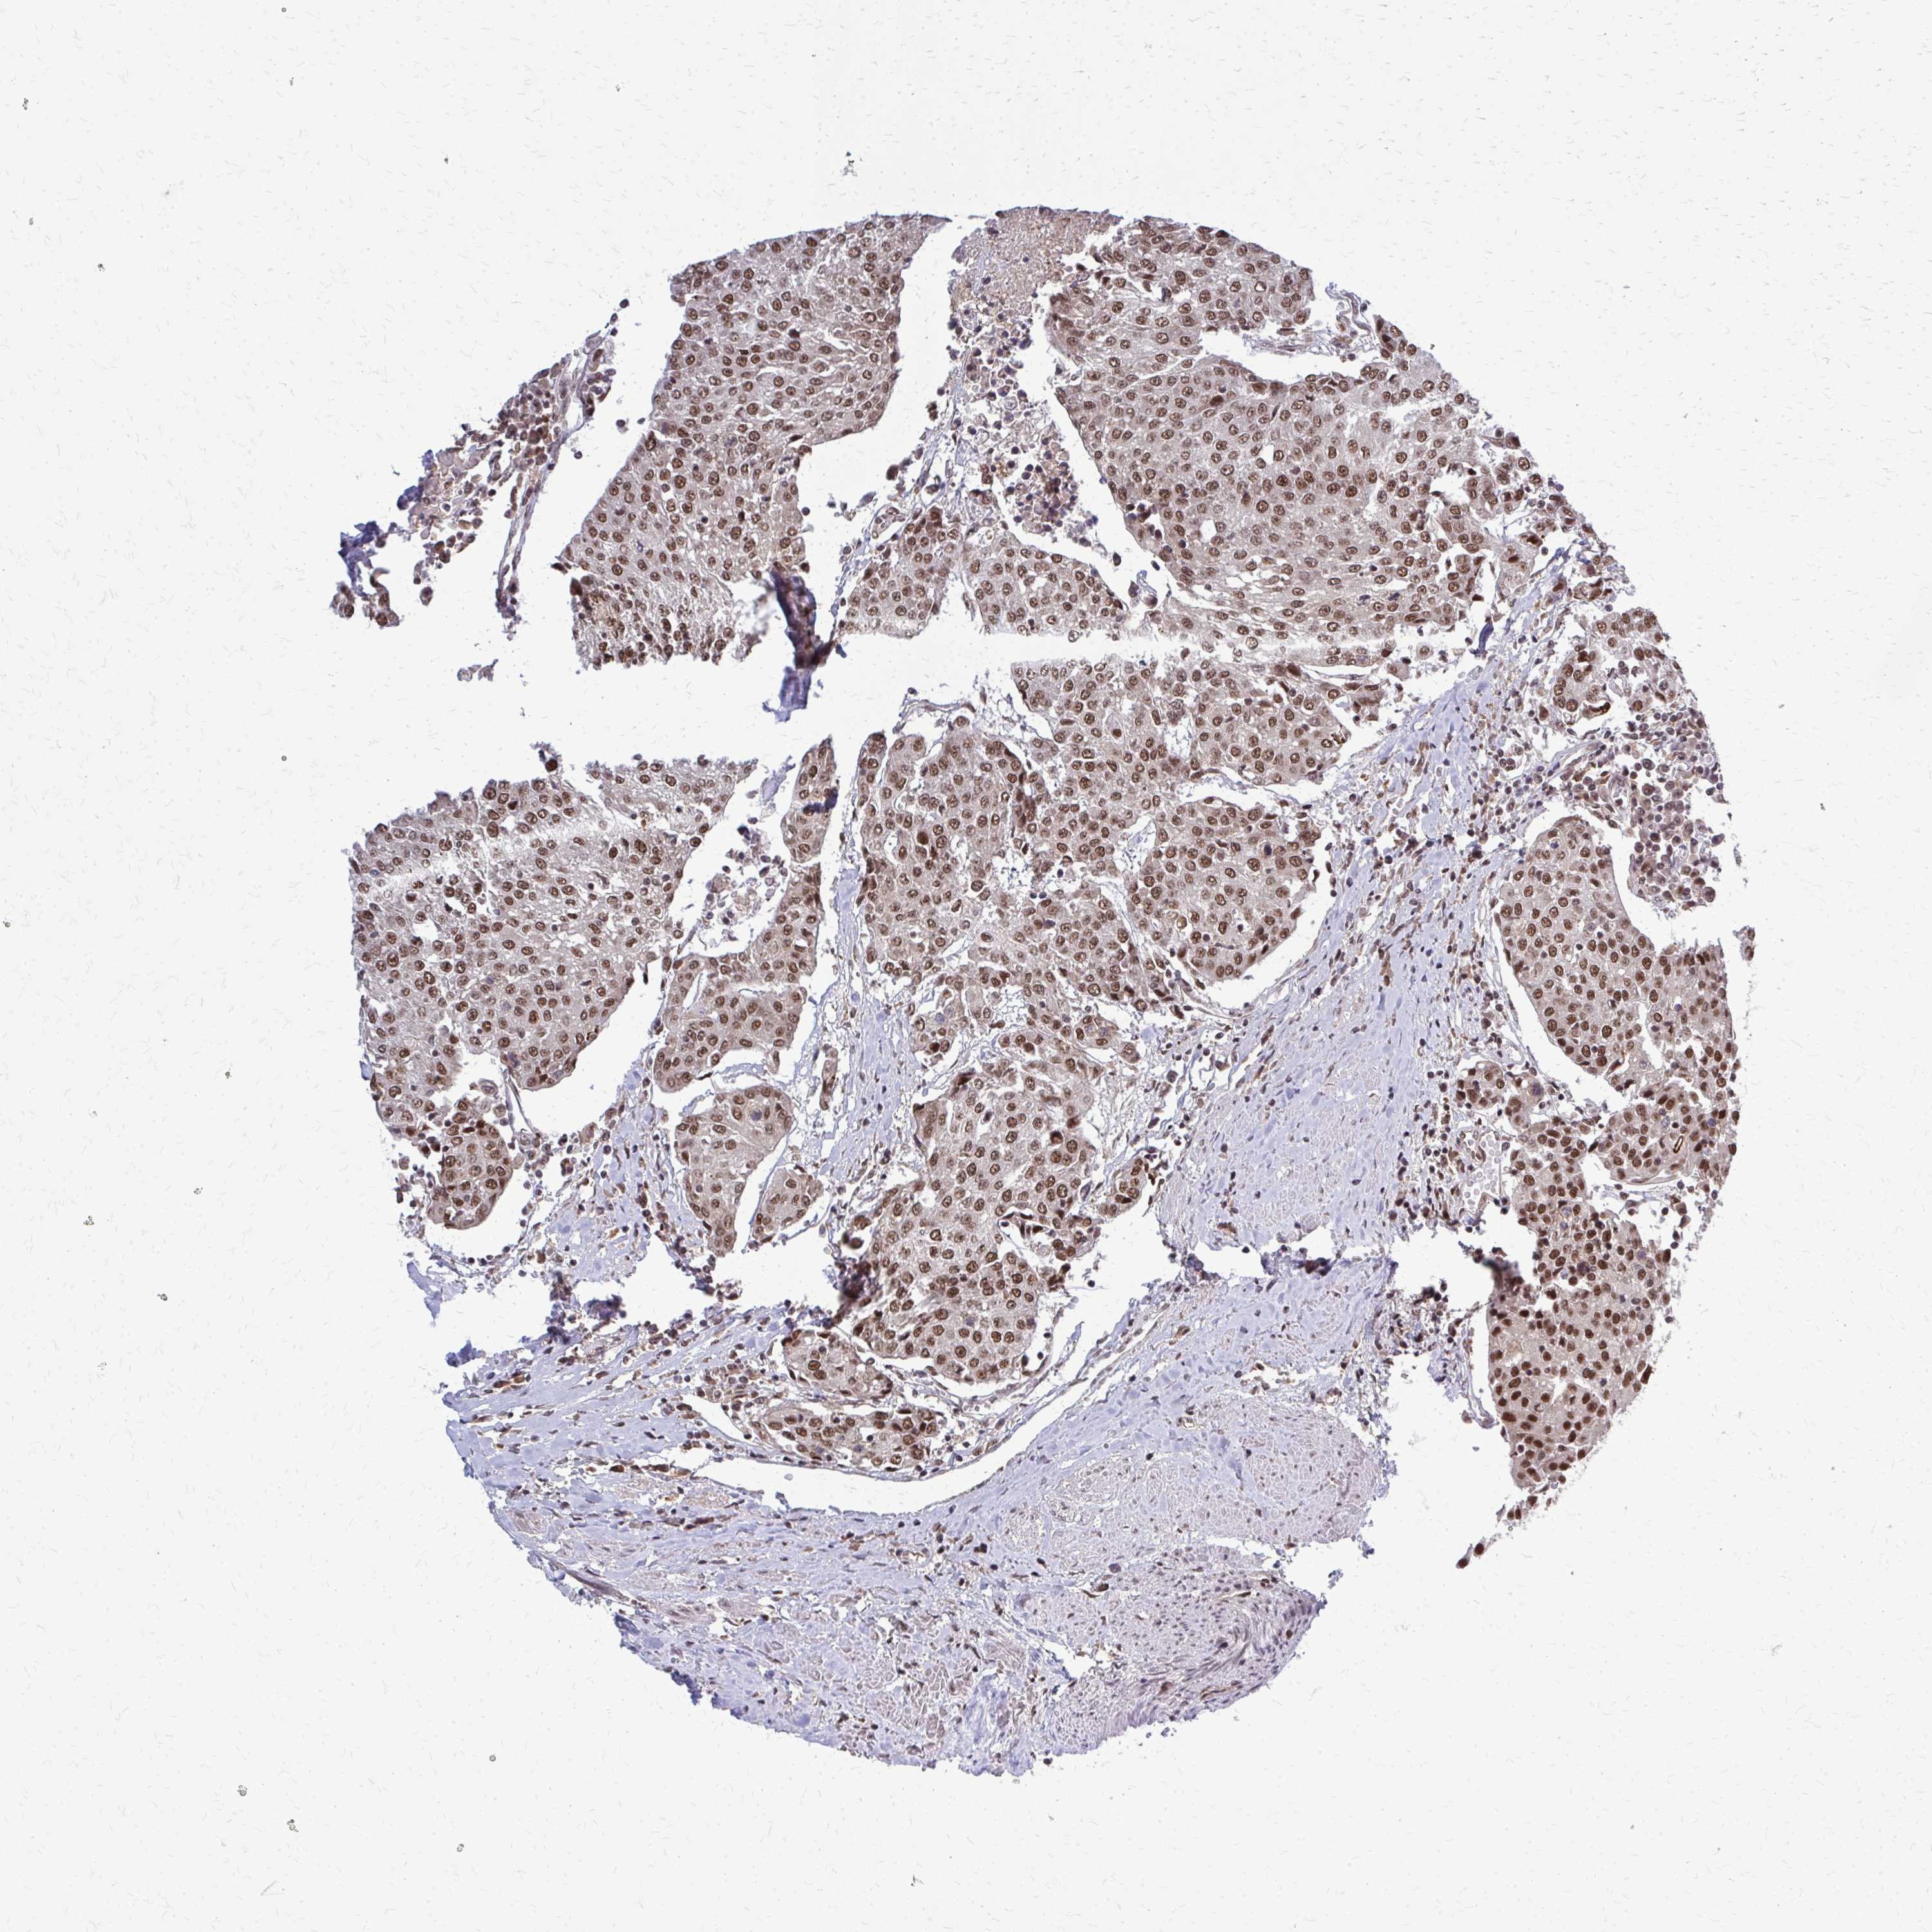

UROTHELIAL CANCER - Protein expressioni

A mouse-over function shows sample information and annotation data. Click on an image to view it in a full screen mode. Samples can be filtered based on level of antibody staining by selecting one or several of the following categories: high, medium, low and not detected. The assay and annotation is described here.

Note that samples used for immunohistochemistry by the Human Protein Atlas do not correspond to samples in the TCGA dataset.

Antibody stainingi

Antibody staining in the annotated cell types in the current human tissue is reported as not detected, low, medium, or high, based on conventional immunohistochemistry profiling in selected tissues. This score is based on the combination of the staining intensity and fraction of stained cells.

Each image is clickable and will lead to virtual microscopy that enables deeper exploration of all samples and also displays staining intensity scores, fraction scores and subcellular localization as well as patient and tissue information for each sample.

Antibody HPA052052

Antibody CAB005583

Antibody CAB072336

Urothelial carcinoma, High grade

Urothelial carcinoma, Low grade

Urothelial carcinoma, NOS